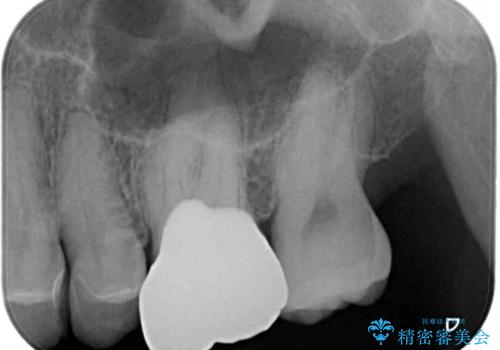

セラミッククラウンを装着する前に仮歯を装着しましたが、その時点で痛みはほぼ改善され、セラミッククラウン装着後には痛みが感じることはもちろん、見た目にも気になる点はなくなりました。